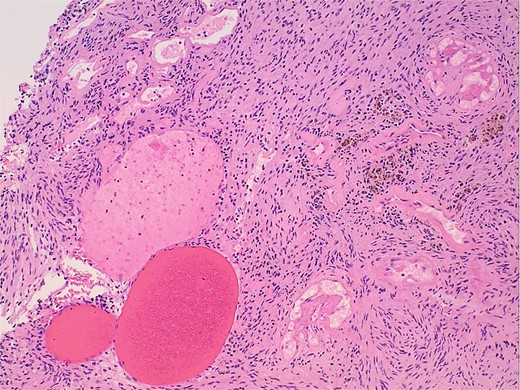

Gross examination and cut sections revealed fragments of tan–white to tan–yellow tissue with some areas of hemorrhage measuring from 1.1 to 3.6 cm in the greatest dimension. Histopathological examination of the excised mass confirmed the diagnosis of a retroperitoneal schwannoma, characterized by S100 positivity (Fig. 3) and degenerative changes, including hemorrhage, hemosiderin, and cystic degeneration (Fig. 4), nuclear atypia (Fig. 5), and perivascular hyalinization (Fig. 6).

Photomicrograph of diagnostic histopathology showing cystic degeneration and hemorrhage with hemosiderin laden macrophages.